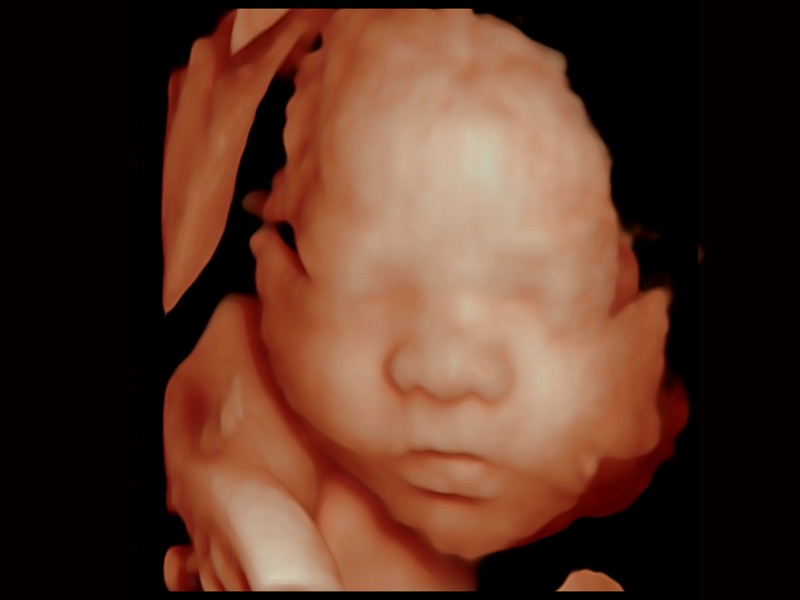

三维光影成像技术采用新型的渲染方式,增强边缘信息,使得轮显示清晰完整,为临床提供丰富、直观的三维结构,提供临床诊断准确性。

妇产科应用